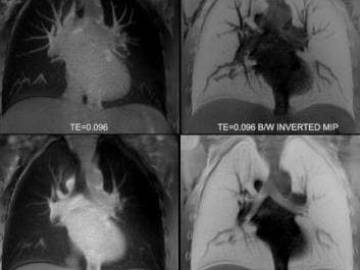

МР-томограммы легких и бронхов представляют собой объемные трехмерные изображения, благодаря которым специалисты могут детально изучить состояние органов со всех сторон и под любым углом и воссоздать анатомическую картину происходящих в них патологических процессов. Для нормального функционирования бронхо-легочной системы характерны следующие показатели:

При наличии той или иной патологии на снимках обнаруживаются участки затемнения или засветления различной величины и интенсивности, по которым врачи-рентгенологи выносят заключение о характере заболевания.

Сами легкие МРТ визуализирует хуже, поскольку этот орган находится в постоянном движении, в нем мало воды и много воздуха. Зато при магнитно-резонансной томографии хорошо оцениваются соседние мягкие ткани, сосудистая и лимфатическая система. Поэтому она широко используется как уточняющая форма обследования после КТ легких для диагностики онкологических процессов в соседних органов средостения, саркоидоза и туберкулеза.